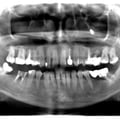

Руйнування зубів - результат тривалого користування бюгельними знімними протезами